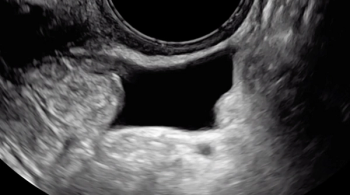

Pressure is being applied to the uterus by the ultrasound operator’s non-scanning hand, eliciting smooth sliding of the posterior uterine serosa over the bowel. Some fluid is noted within the rectouterine pouch, which often suggests a non-obliterated pouch

A hypoechoic deep endometriosis nodule is noted within the hyperechoic uterosacral ligament, infiltrating the parametrium

A hypoechoic deep endometriosis nodule is noted within the hyperechoic uterosacral ligament.

A hypoechoic deep endometriosis nodule is noted within the hyperechoic uterosacral ligament. In this case, there is an ovary containing an endometrioma fixed to the uterosacral ligament nodule.